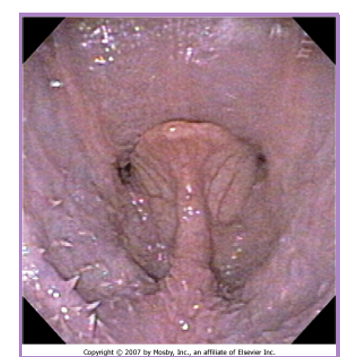

BOAS Elongated soft palate

palate extends >1-3mm beyond the epiglottis

subjective evaluation - caution

can use tonsils as a guideline

laryngeal mucosa becomes inflamed

why a concern

laryngeal edema = airway obstruction

chronic upper airway stress

like having curtains over open window decreased airflow the soft palate drops down over the epiglottis

surgical technique (staphylectomy/palatoplasty) - shortening the soft palate

remove elongated portion of the palate

trim to level of tonsils / just past tip of epiglottis